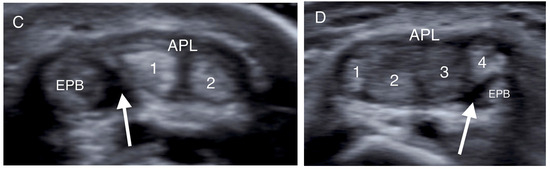

- Choi, S.J.; Ahn, J.H.; Lee, Y.J.; Ryu, D.S.; Lee, J.H.; Jung, S.M.; Park, M.S.; Lee, K.W. De Quervain Disease: US Identification of Anatomic Variations in the First Extensor Compartment with an Emphasis on Subcompartmentalization. Radiology 2011, 260, 480–486. [Google Scholar] [CrossRef]

- Kwon, B.C.; Choi, S.J.; Koh, S.H.; Shin, D.J.; Baek, G.H. Sonographic Identification of the Intracompartmental Septum in de Quervain’s Disease. Clin. Orthop. Relat. Res. 2010, 468, 2129–2134. [Google Scholar] [CrossRef]

| Intracompartmental septum | 27 (54%) |

| Double groove | 12 (24%) |